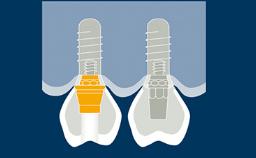

Transitional prostheses play an important role in replacing missing teeth during implant therapy, up to the point when the implants are ready to be restored.

Implant therapy often involves several clinical and laboratory stages, and transitional prostheses seek to ensure that the patient is comfortable on both an esthetic and a functional level throughout the duration of treatment.

There are a number of options for transitional prostheses, both fixed and removable.